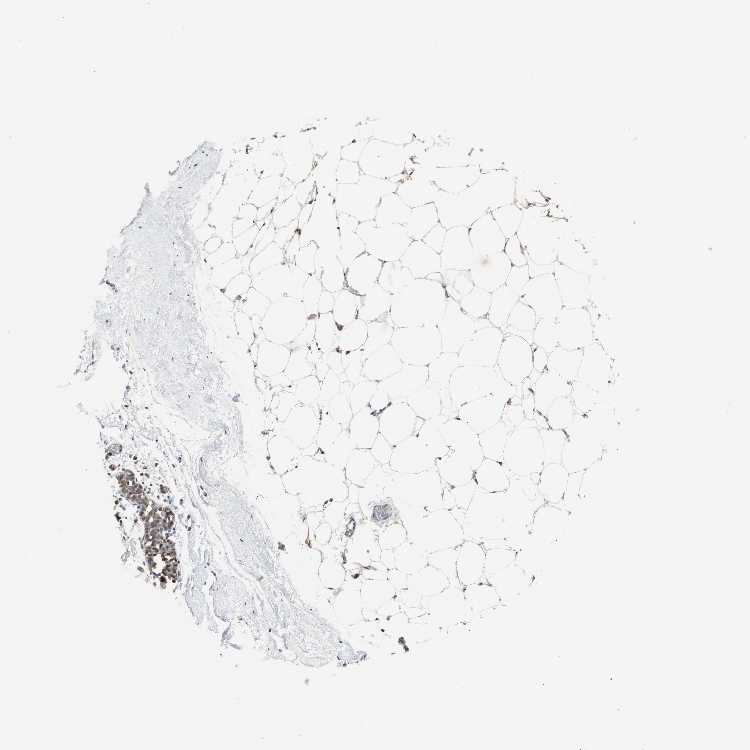

BREAST - Antibody stainingi

Antibody staining in the annotated cell types in the current human tissue is reported as not detected, low, medium, or high, based on conventional immunohistochemistry profiling in selected tissues. This score is based on the combination of the staining intensity and fraction of stained cells.

Each image is clickable and will lead to virtual microscopy that enables deeper exploration of all samples and also displays staining intensity scores, fraction scores and subcellular localization as well as patient and tissue information for each sample.

Antibody HPA006471

Adipocytes Low

Glandular cells High

Myoepithelial cells High